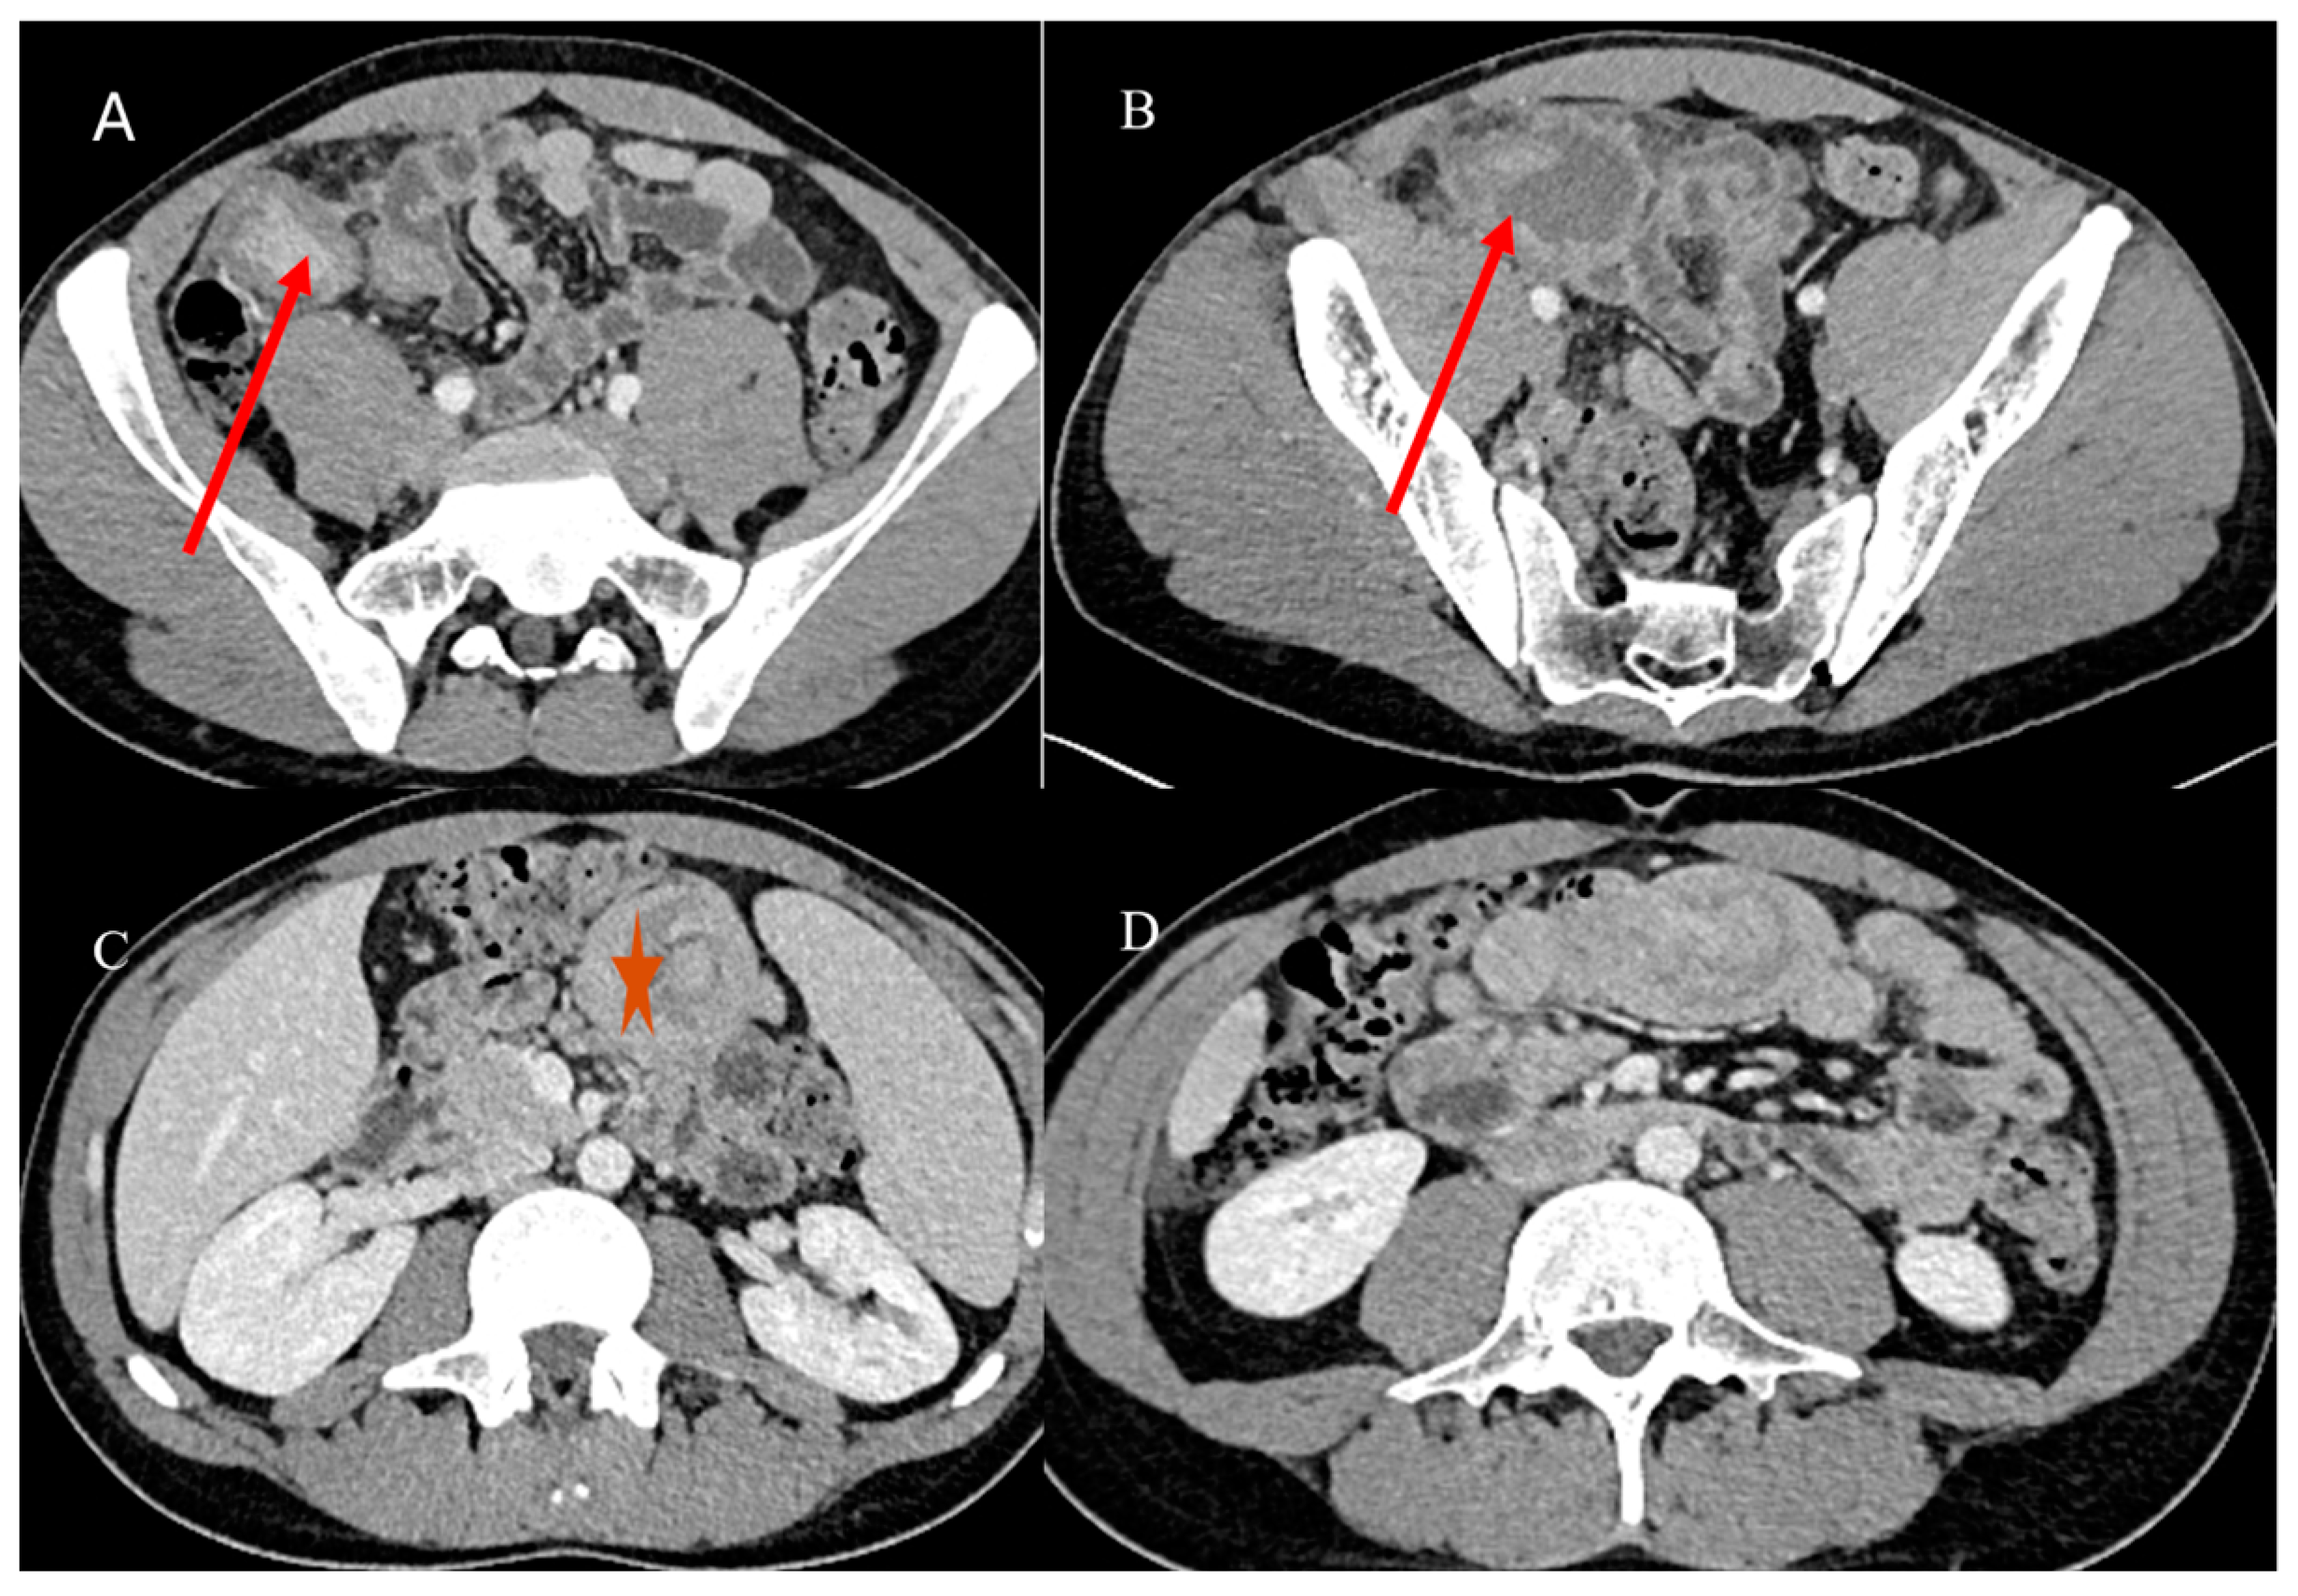

- Marsicovetere, P.; Ivatury, S.J.; White, B.; Holubar, S.D. Intestinal intussusception: Etiology, diagnosis, and treatment. Clin. Colon. Rectal Surg. 2017, 30, 30–39. [Google Scholar] [CrossRef] [PubMed]

- Kim, Y.H.; Blake, M.A.; Harisinghani, M.G.; Archer-Arroyo, K.; Hahn, P.F.; Pitman, M.B.; Mueller, P.R. Adult intestinal intussusception: CT appearances and identification of a causative lead point. Radiographics 2006, 26, 733–744. [Google Scholar] [CrossRef]

- Choi, S.H.; Han, J.K.; Kim, S.H.; Lee, J.M.; Lee, K.H. Intussusception in adults: From stomach to rectum. AJR Am. J. Roentgenol. 2004, 183, 691–698. [Google Scholar] [CrossRef]

- Panzera, F.; Di Venere, B.; Rizzi, M.; Biscaglia, A.; Praticò, C.A.; Nasti, G.; Mardighian, A.; Nunes, T.F.; Inchingolo, R. Bowel intussusception in adult: Prevalence, diagnostic tools and therapy. World J. Methodol. 2021, 11, 81. [Google Scholar] [CrossRef] [PubMed]